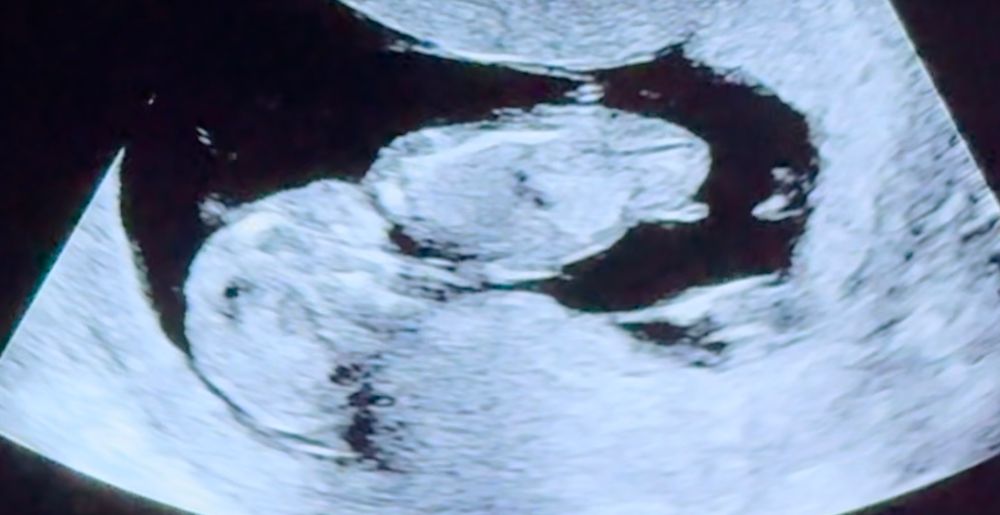

Мальчик или девочка?)

Срок 13+2 по ктр 😁😁😁 Я все узи снимала на видео, вот скриншоты)))

Узист предположил девочку) так ли это?)🥹🥹🥹